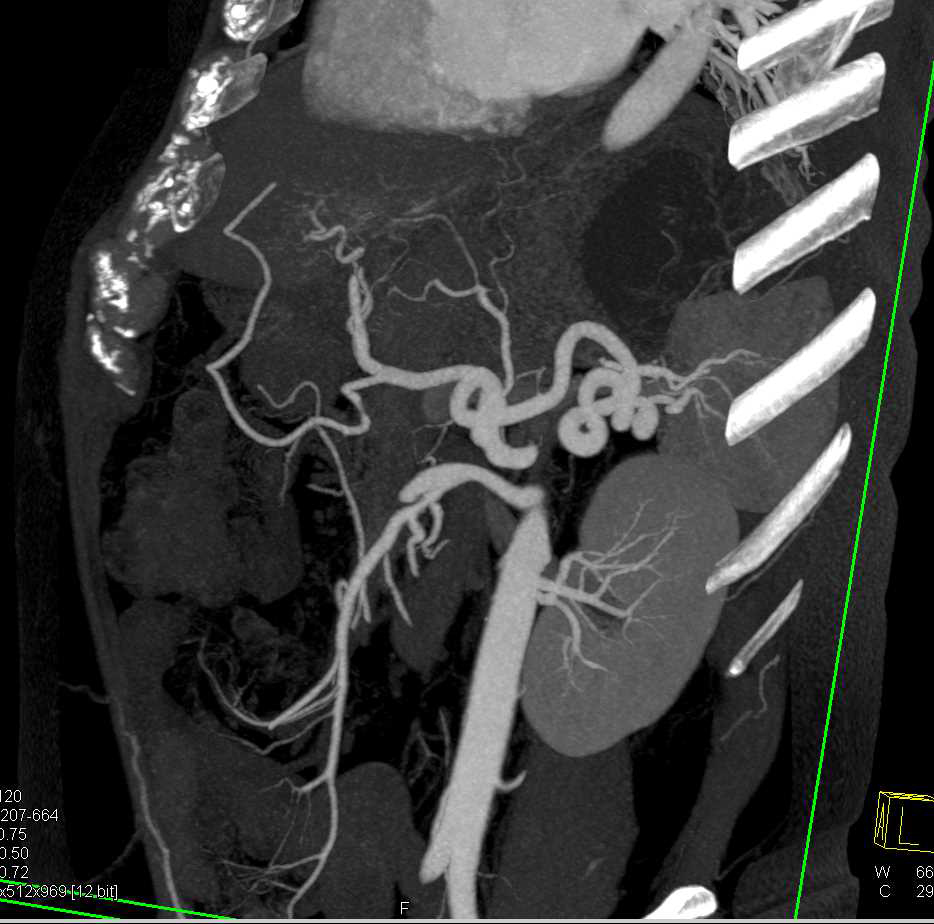

Aneurysm of the Celiac Artery